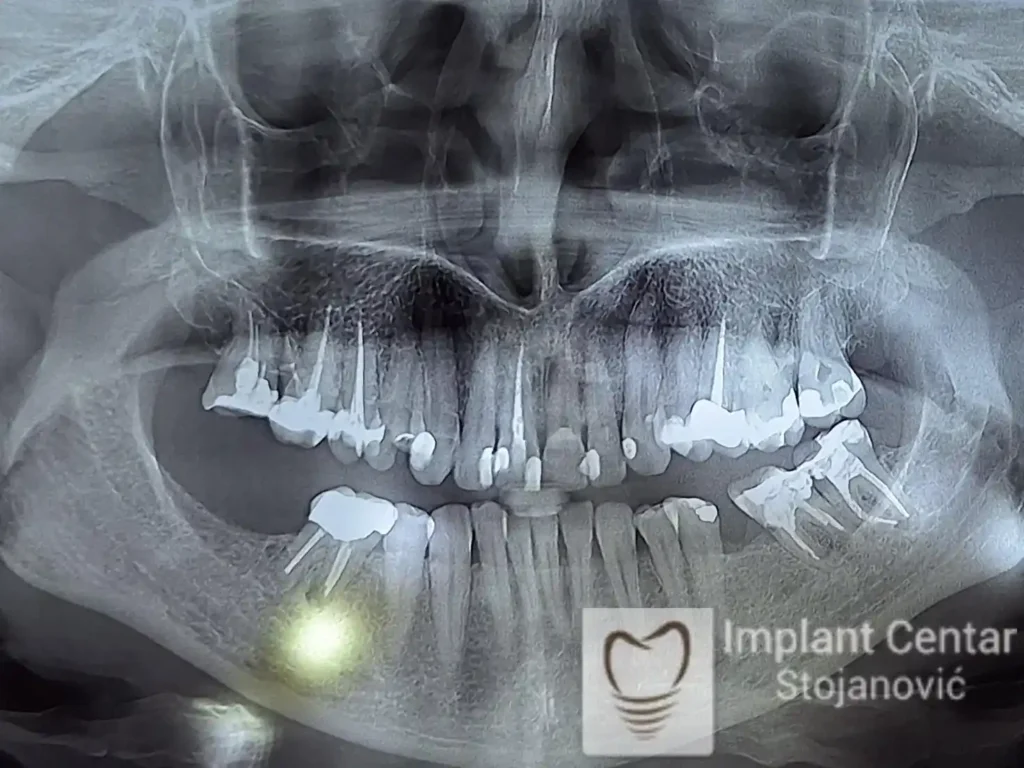

Nakon vađenja zuba, ugrađeni su implantati. Na slici 3 prikazan je ortopan snimak sa ugrđenim implantatima. Tokom perioda osteointegracije, pacijent je bio zbrinut fiksnim privremenim krunicama na implantatima, koje su izrađene samo dva dana nakon hirurške intervencije.

Na slikama 5. i 6. prikazan je izgled definitivnih cirkonijum-keramičkih mostova na implantatima.